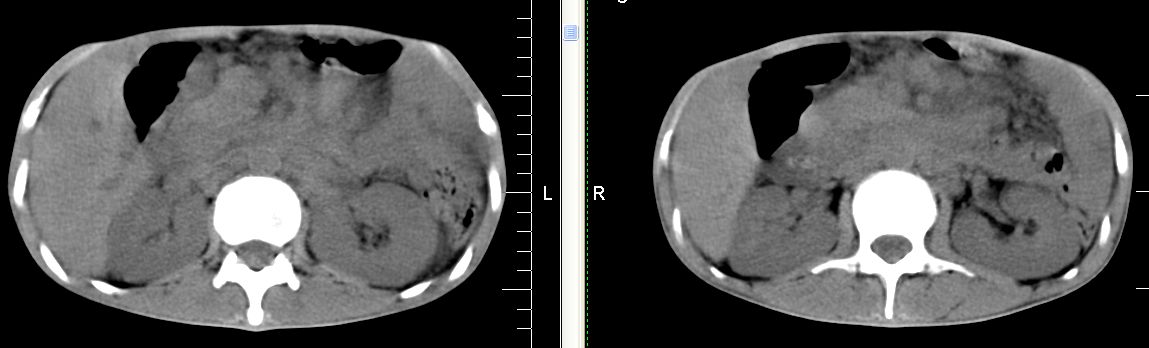

m 29 肺tb患者,目前诉下腹疼痛 t39度 腹韧,有压痛,可触及3x4cm包块

脾脏多发类圆形低密度影,建议增强扫描。

脾脏多发类圆形低密度影并腹水,建议增强扫描。

脾脏多发低密度灶,肠系膜及腹膜后见多发大小不等结节状影,右结肠旁沟见低密度影,结合病史考虑:脾结核,肠系膜及腹膜后淋巴结结核,少量腹水。

右侧结肠亦可见病变,腹膜后可见多发增大的淋巴结影,脾脏内示多个低密度结节灶,结合病史考虑结核性病变。

脾脏多发低密度灶,腹膜后及肠系膜根部多发淋巴结淋巴结肿大并部分相互融合,考虑tb.图象窗宽\\窗位没调整好,不清晰,另外,肠道准备亦不理想.

脾脏多发低密度灶,左侧肾上腺见块状病灶,密度不均,盲肠升结肠肠壁明显增厚,左下腹似可见肠壁增厚,肠系膜及腹膜后见多发大小不等结节状影,右结肠旁沟见低密度影,1淋巴瘤可能大,2结合病史考虑:脾结核,左侧肾上腺结核,肠系膜及腹膜后淋巴结结核,少量腹水待除外,